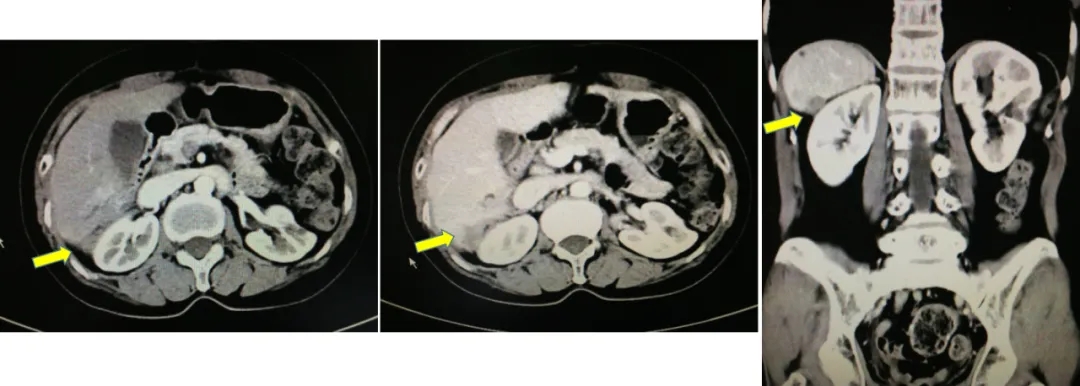

2013.5.6在我院(中国科学院大学附属肿瘤医院)检测CA125水平为298.8U/ml。CT:胸部(-),肝肾隐窝异常信号,脾脏前内方囊性占位灶,考虑转移灶;肠系膜上动脉水平、腹主动脉偏左侧结节灶;盆腔(-)。

2013.5.10 PET-CT:肝肾隐窝、脾肾间隙、脾门旁、腹膜后可见斑片状、囊实性及结节状影,实质部分FDG代谢增高,考虑转移。

2013.5.10 PET-CT检查结果